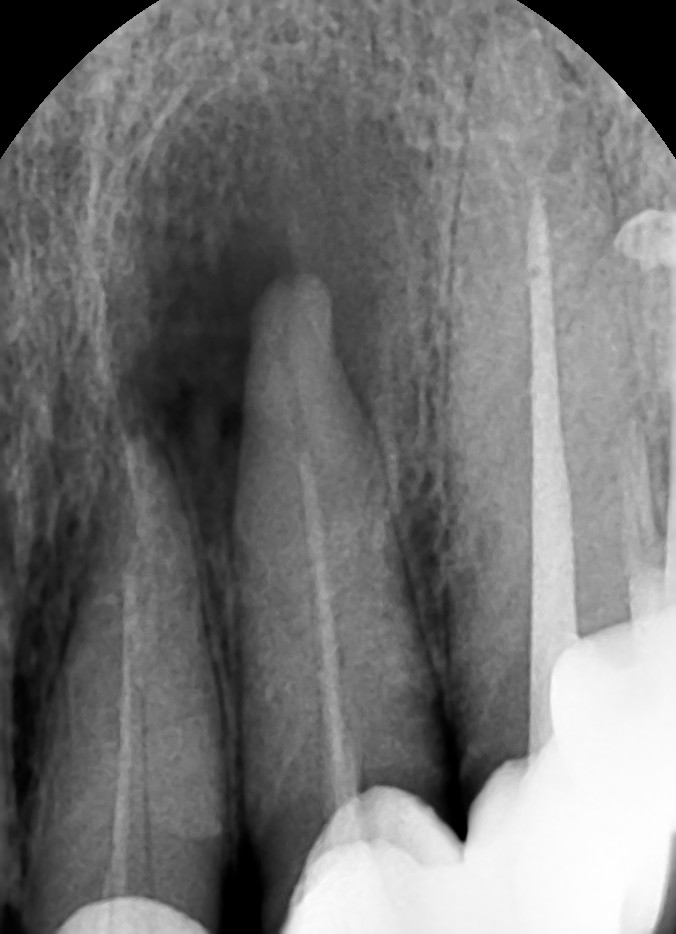

앞니뼈가 없는데 임플란트 가능한가요?

오늘은 부천 연세퍼스트치과에서 앞니뼈이식을 동반한 임플란트 수술 진행한 케이스에 대해 글을 작성하려...